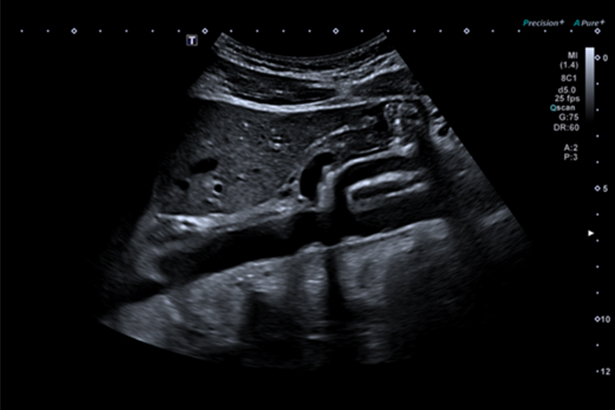

依托Aplio a450先進的成像平臺,在使用凸陣探頭進行腹部成像時,可以大幅擴展成像角度,得到更清晰和全面的視野,幫助準確診斷。